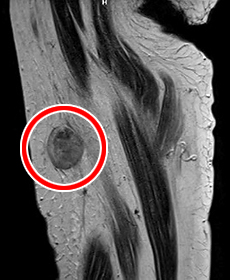

レントゲンやCT、MRIなどの画像診断を行います。確定診断には組織の病理検査が必要です。病気のある部位や状態により組織を採取する方法を決めます。

悪性腫瘍(→)のMRI画像